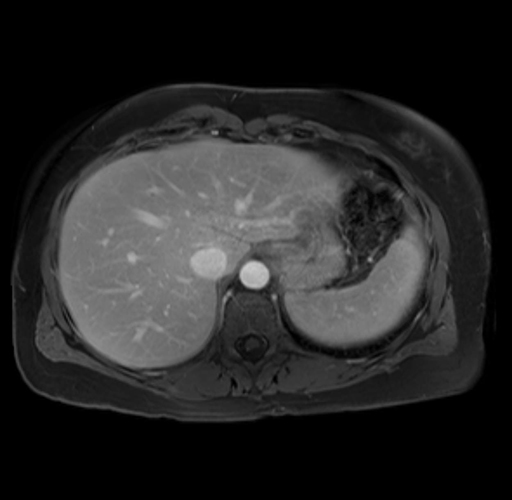

Imaging Analysis

Look through the patient's CT scan to identify any areas of concern for the necessary procedure.

Based on your CT findings, which issue(s) are present and would give reason for "planned slowing down moment(s)" in this case?